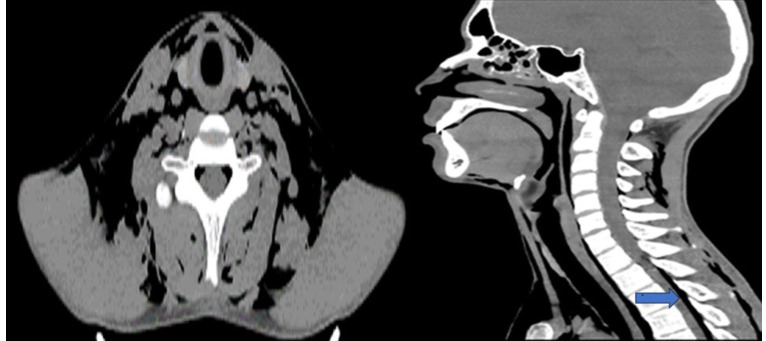

1939 年,哈曼氏综合征(Hamman´s Syndrome)又称自发性气胸,其特征是出现气胸、皮下气肿和气臌。据认为,它是由阴道分娩时的气压创伤引起的,导致肺泡膜破裂和随后的漏气。临床表现通常没有特异性。根据症状严重程度和并发症的不同,治疗策略也有所不同,高浓度氧疗可促进空气吸收。我们介绍了一名 18 岁男性患者的病例,该患者有支气管哮喘和吸烟史,强调了在类似病例中提高对哈曼综合征认识的必要性。及时诊断和适当治疗对于预防或快速处理潜在的危及生命的并发症至关重要。在男性患者中诊断这种综合征尤其具有挑战性,因为它最初与阴道分娩的并发症有关,可能导致较差的预后。

In 1939, Hamman´s syndrome, also know as spontaneous pneumomediastinum, was characterized by the presence of pneumothorax, subcutaneous emphysema, and pneumorrhachis. It is believed to arise from barotrauma during vaginal labor, causing alveolar membrane rupture and subsequent air leakage. Clinical manifestations are often nonspecific. Management strategies vary based on symptom severity and complications, high-concentrations oxygen therapy promoting air absorption. We present the case of an 18-year-old male patient with a history of bronchial asthma and tobacco use, underscoring the need for heightened awareness of Hamman´s syndrome in similar cases. Prompt diagnosis and appropriate management are crucial to prevent or quickly address potential life-threatening complications. Diagnosing this syndrome in male patients can be particularly challenging, as it was initially associated with complications from vaginal labor, potentially leading to poorer outcomes.